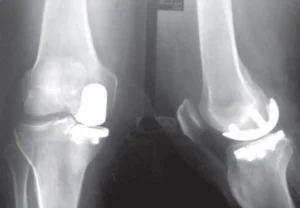

Osteotomia

Técnica utilizada para corrigir o mau alinhamento ósseo e assim, aliviar a dor, através da transferência de carga de áreas danificadas na articulação para áreas mais saudáveis. Indicada para pacientes jovens e ativos, para que possam continuar com as suas atividades de alto impacto e/ou recreativas.